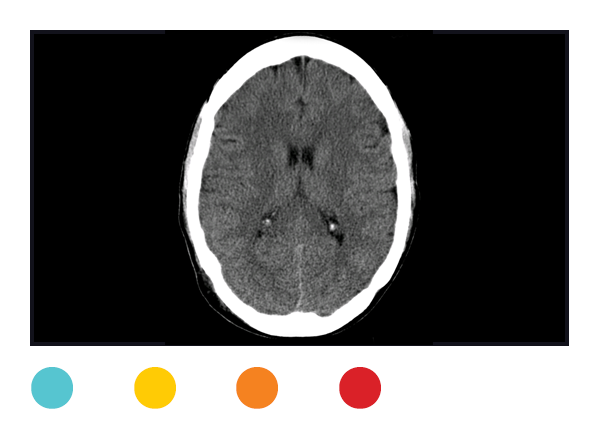

CT

Computed tomography uses a pencil-thin X-ray beam to create a series of images from multiple angles, which are then transferred to a computer, creating a 3D image that can be enlarged and rotated onscreen. Excellent for looking at soft tissue. Radiation exposure: minimal to high.

CT of head

2

8 months

Not needed for most head injuries. CTs usually aren't needed for a concussion.